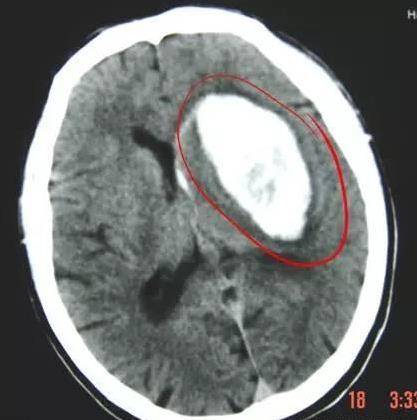

腦出血,是中風的另一種,稱為出血性腦卒中,簡單說,就是腦子裡的血管破裂出血了。

腦出血,多見於60歲以下,常在活動、情緒激動時,導致發病。

腦出血的症狀較重,且 預後相對不佳,一般常見有頭痛、頭暈、嘔吐等症狀,血壓明顯升高,嗜睡、昏迷甚至出現癲癇,其 身亡率相對較高,復發率相對較低。